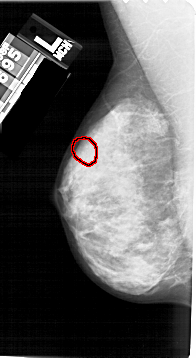

A_1338_1.LEFT_MLO

FILE: A_1338_1.LEFT_MLO.OVERLAY

TOTAL_ABNORMALITIES 1

ABNORMALITY 1

LESION_TYPE CALCIFICATION TYPE AMORPHOUS DISTRIBUTION CLUSTERED

ASSESSMENT 4

SUBTLETY 4

PATHOLOGY BENIGN

TOTAL_OUTLINES 1

BOUNDARY